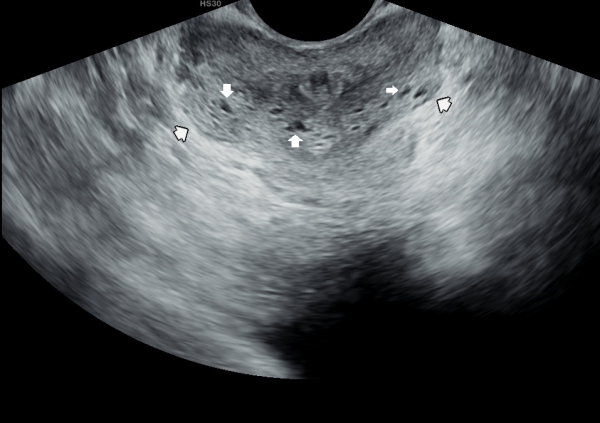

전립선의 표적치료후 고환의 미석증이 없어지고 고환이 커진 경직장 전립선 초음파 자료 입니다.(주2회 표적치료)

This is a transrectal ultrasound image showing the improvement after targeted prostate treatment.

After twice-weekly targeted treatment, testicular microlithiasis disappeared, and the testicles increased in size.